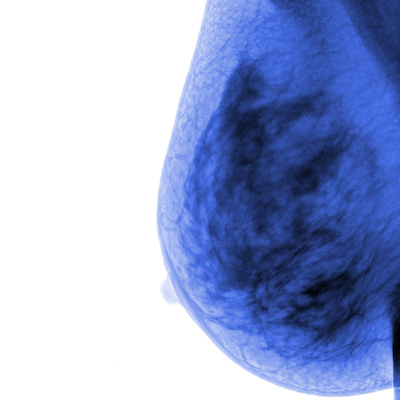

Dembrower and colleagues sought to do just that in their study, testing the performance of a commercial AI system (Insight, version 1.1.6, Lunit) in the ScreenTrustCAD study. This was a prospective, population-based, paired-reader, noninferiority study performed at the Capio Sankt Göran Hospital in Stockholm, Sweden, between 2021 and 2022. The team wanted to evaluate the noninferiority of double reading by one radiologist plus AI compared with standard-of-care double reading by two radiologists. It also explored single reading by AI alone and triple reading by two radiologists plus AI compared with the European standard-of-care double reading by two radiologists.

The researchers included data from 55,581 women ages 40 to 74 who underwent regular mammography screening. Of these, 269 women (0.5%) were diagnosed with screen-detected breast cancer based on an initial positive read.